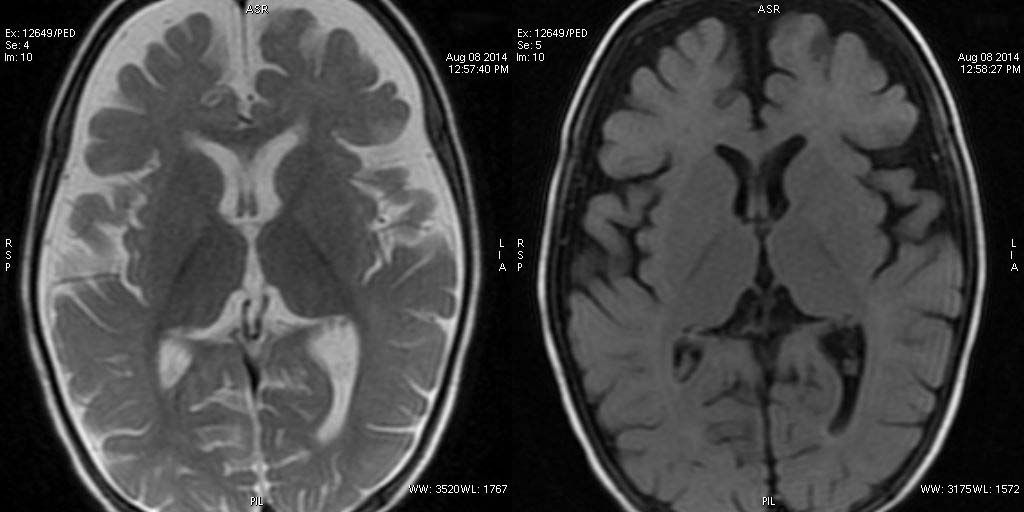

Non specific cerebral atrophy of different grades was observed in all cases except one. In [Table/Fig-2], reduced thickness of corpus callosum was observed in six patients on MRI brain studies. ITS cases who had severe wasting, three out of four showed evidence of cerebral atrophy; all three children with moderate wasting had evidence of cerebral atrophy. Cerebral atrophy was observed in all children with stunting as well as in children having normal height for age and sex. Some patients (6/10) had mild to moderate ventricular dilatation and most patients (9/10) had prominence of Sylvian sulcus. Ventricular dilatation and prominence of Sylvian sulcus had correlation with the grades of cerebral atrophy in all cases [Table/Fig-3,4,5,6,7,8,9,10,11 and 12].

T2W sagittal, axial FLAIR and T2W sequence revealing diffuse atrophy and reduced volume of corpus callosum. Hyperintensity on T2W sequence suggestive of marginally poor myelination.

T2W sagittal, axial and axial FLAIR sequence showing significant diffuse atrophy and reduced volume of corpus callosum. No evidence of poor myelination appreciable.

T2W axial, sagittal and axial FLAIR sequence revealing significant diffuse atrophy and reduced volume of corpus callosum. Prominence of sylvian fissure and CSF spaces noted. Mild cerebellar atrophy is appreciable in sagittal T2W image.

T2W axial, sagittal and axial FLAIR sequence revealing significant atrophy involving the frontal and temporal lobes and reduced volume of corpus callosum. Faint T2W hyperintensity of white matter is compatible with age.

T2W axial, sagittal and axial FLAIR sequence revealing mild cerebral atrophy and normal corpus callosum.

T2W axial, sagittal and axial FLAIR sequence revealing significant atrophy and reduced volume of corpus callosum.

T2W and axial FLAIR sequence revealing significant atrophy involving the frontal and temporal lobes.

T2W axial, sagittal and axial FLAIR sequence revealing significant atrophy involving the frontal and temporal lobes. The appearance of corpus callosum is within normal limits.

T2W axial, sagittal and axial FLAIR sequence revealing significant atrophy predominantly involving the frontal and temporal lobes and reduced volume of corpus callosum. Also, noted marginally poor myelination, predominantly peritrigonal white matter.

Neuroimaging was limited to pneumoencephalography in the past [4] but with recent advances in radio diagnostic imaging, studies have come up with neuroimages in ITS cases [3,6,18] and revealed non specific diffuse cerebral atrophy. This study also depicted different grades of cerebral atrophy along with reduced thickness of corpus callosum representing loss of white matter. Presence of ventricular enlargements in many patients in the present study also lends support to presence of cerebral atrophy.